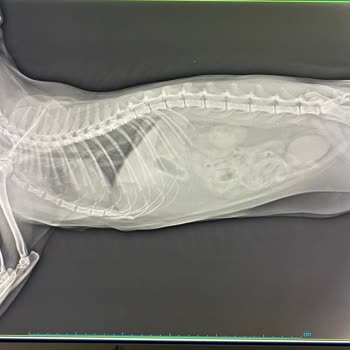

Nachdem ich dieses Futter meiner Katze gegeben hatte, wurde sie krank. Ich brachte sie zum Tierarzt, der eine Lebensmittelvergiftung diagnostizierte und sagte, dass sie vom Nassfutter stamme. Nach zwei Injektionen kehrten wir nach Hause zurück. Als es meiner Katze schlechter ging, brachte ich sie er...